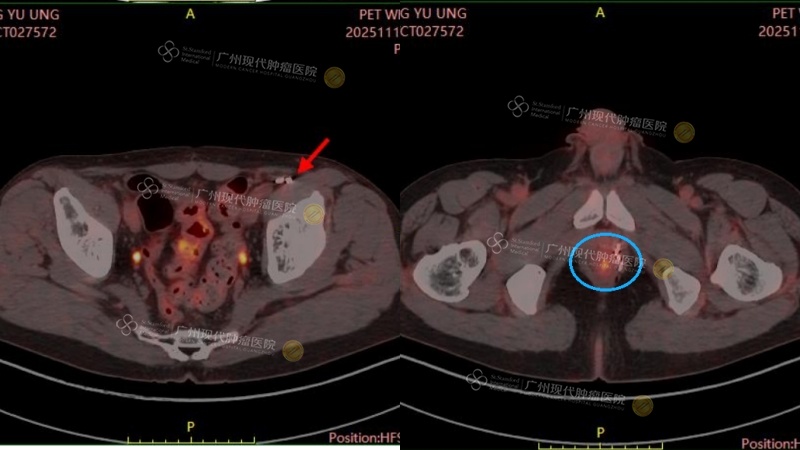

根据2025年11月12日的最新CT影像学评估结果显示:陈先生的前列腺肿瘤及淋巴结病灶均已基本完全失活!这个“好消息”让陈先生和家属倍感欣慰,笑容也愈发多了起来。我们相信,这个阶段性的胜利不仅源于先进技术的精准发力,更是陈先生本人坚韧乐观、积极配合的结果。前路光明,我们满怀信心,与他一同期待下一个好消息。

(2025年11月12日,最新CT结果:前列腺肿瘤及淋巴结转移病灶均已基本完全失活)